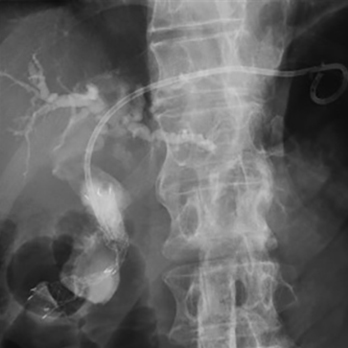

胆管炎・胆嚢炎・閉塞性黄疸に対するERCP・EUSによる胆道ドレナージ術・経皮経肝的胆道ドレナージ術(PTBD・PTGBD)

胆管結石・膵石に対する内視鏡的結石除去術

経口胆管鏡と電気水圧衝撃波結石破砕装置(EHL)による胆管結石破砕術

術後再建腸管の胆管結石に対するバルーン小腸内視鏡による胆管結石除去術